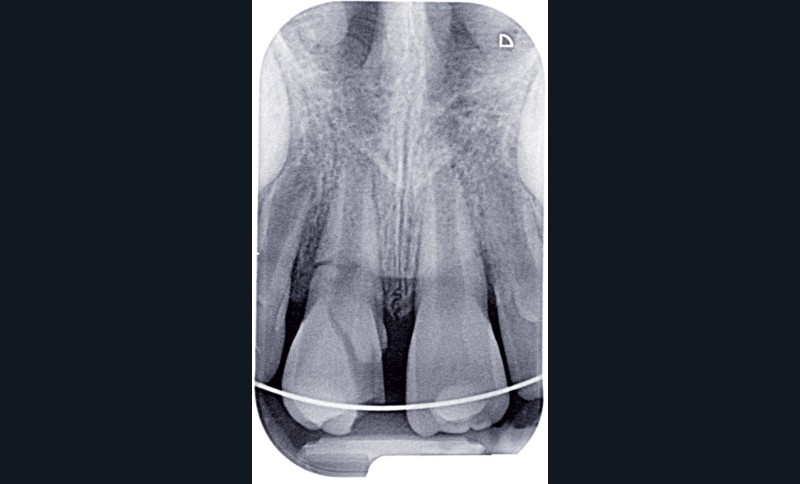

a à d Jeune patiente âgée de 8 ans, adressée suite à un traumatisme survenu 3 semaines auparavant, pour l’extraction de sa 21. La vue clinique montre un saignement ligamentaire, une mobilité coronaire et une fracture coronaire amélodentinaire longitudinale partant de l’angle mésial et se poursuivant en direction radiculaire sous-gingivale (a). Un test de vitalité positif indique que la dent est vitale, la radiographie permet de poser le diagnostic de fracture coronoradiculaire, et d’objectiver l’immaturité radiculaire (stade 8 de Nolla) (b). Une contention est mise en place et la plaie dentinaire coronaire est scellée au mieux par collage afin de limiter le risque d’une complication infectieuse (c). A 15 jours la dent est vivante et aucune complication n’est apparue (d). La patiente est revue après 3 mois pour déposer la contention, le test de vitalité est positif, et la radiographie de contrôle montre une apexogenèse en cours (e). Cependant la gencive s’est invaginée dans le trait de fracture (f). La zone est débridée sous microscope (g) puis scellée et reconstituée à l’aide d’un adhésif SAM et d’un composite fluide (h). Le contrôle radiographique à 6 mois est satisfaisant (i). Ce cas clinique illustre le fort potentiel des pulpes jeunes et du ligament alvéolodentaire à résister aux agressions et à assurer les fonctions dentinogénétiques et l’édification radiculaire.